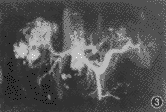

图2 手术证实肝右前叶肝细胞肝癌。CTP图像(MIP)可见门静脉右前支局部癌栓形成(箭),表现为局限性不规则充盈缺损,余各分支显影良好